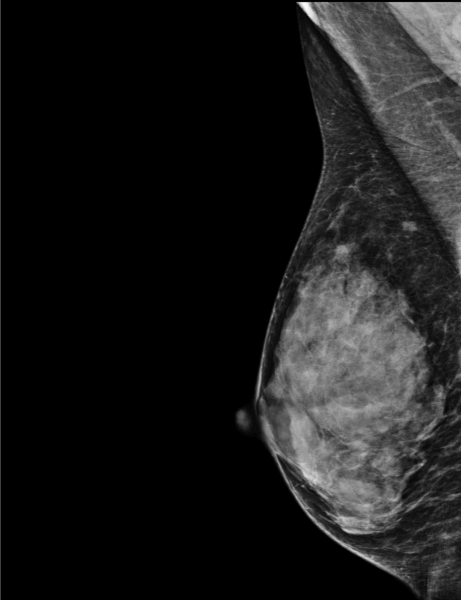

Screening mammogram on dense breasts (D) in 2020.

Here, a lobulated asymmetry of 6.5 mm in diameter without associated calcifications is detected on the right breast, 9 cm from the nipple.

Another mammo and ultrasound confirm the presence of the lesion at 9.30.

The biopsy reveals the presence of an invasive ductal carcinoma (IDC).